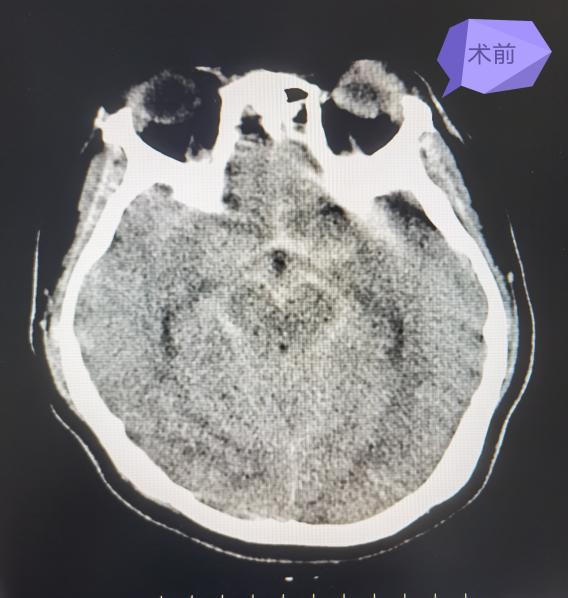

最近,患者苏女士突发意识不清,伴右侧肢体偏瘫,肌力1级,来我院急诊医学科就诊,头部CT提示蛛网膜下腔出血,Hunt-Hess(分级)3级。经神经外科荆泽林主治医师会诊后立即收住入院同时向科主任王伟志汇报患者病情,科室集体讨论后考虑颅内动脉瘤破裂致蛛网膜下腔出血,急行脑血管造影术。

术前